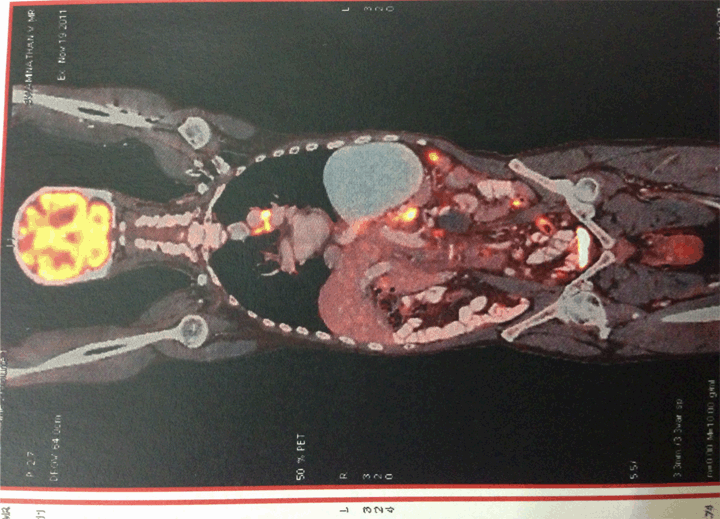

A 72-year old male, without any known comorbidities, was admitted to our hospital due to altered mental status, weakness, anorexia, hematemesis and urinary incontinence for three days. He complained of abdominal distension and dyspepsia for the last two years. There was a loss of appetite and weight of about 10 kg. At the time of admission to hospital, physical examination revealed blood pressure 110/80 mmHg, tachycardia 120 bpm with no other specific systemic finding. The patient was severely dehydrated, presented with decreased reflexes and his skin showed hyperpigmentation. (Figure 1) Laboratory tests demonstrated hyponatremia (serum sodium 125 mEq/L), hyperkalemia (serum potassium 5.6 mEq/L), anemia (Hb 7.3 g/dL) and mild metabolic acidosis (pH 7.25). The electrocardiogram showed normal QRS complexes. There was a mild rise in serum urea 47 mg/dL and normal serum creatinine levels 0.8 mg/dL. After ruling out tuberculosis and drug induced adrenalitis, computed tomography (CT) scan of chest and abdominal was done. Gastric carcinoma with perigastric, periceliac and para aortic lymphadenopathy along with bilateral metastases of the adrenal glands was found. (Figure 2) We performed a whole body positron emission tomography (PET) scan which further validated the CT findings. (Figure 3) The biopsy showed a moderate to poorly differentiating adenocarcinoma in the gastric antrum. Based on the patient’s clinical status and the laboratory test results, in addition to the magnitude of the adrenal masses, we decided to perform a high dose cosyntropin stimulation test. The serum cortisol level was 420 nmol/L before the intramuscular administration of cosyntropin (250 µg), and 61,438 nmol/L 60 minutes after the administration. These results combined with the elevated levels of adrenocorticotropic hormones (ACTH) 165.7 pg/mL before the administration, and the diagnosis of adrenal insufficiency had been established.

Figure 3: Whole body positron emission tomography scan.